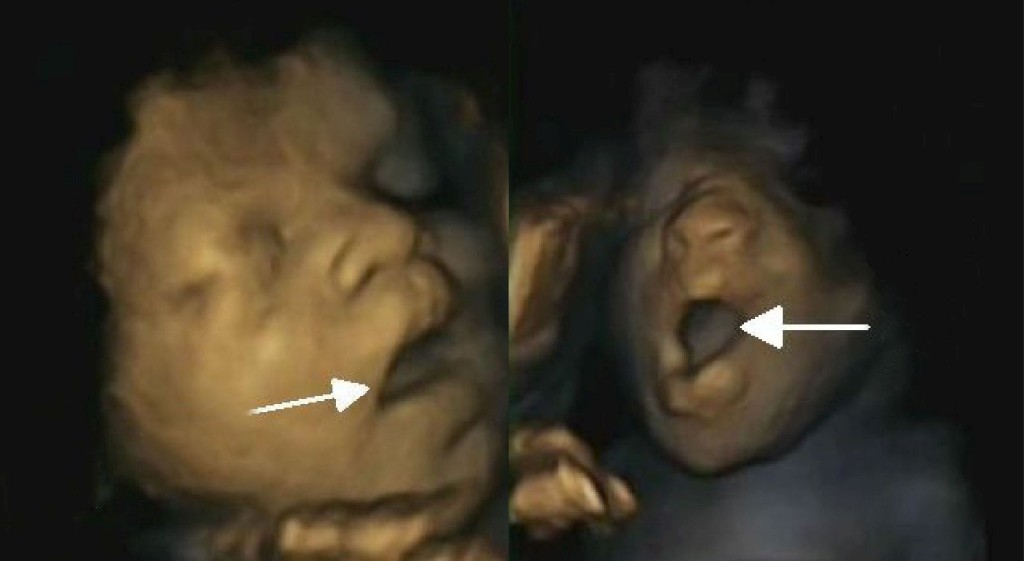

A equipa liderada por Nadja Reissland, do Departamento de Psicologia da Universidade de Durham, estudou 15 fetos – oito raparigas e sete rapazes –, com idades de gestação entre as 24 e as 36 semanas. No total, fizeram 58 ecografias, que permitiam obter gravações em vídeo dos fetos, os cientistas puderam distinguir entre um bocejo (56) e a mera abertura da boca (27) e confirmaram a existência deste movimento nas nossas vidas desde tão cedo.

No bocejo, considera-se que a boca se mantém aberta mais tempo no início do que na parte final. Além desta perspectiva dinâmica do bocejo, difícil de captar noutras ecografias bidimensionais, a sua definição ainda inclui a abertura dos maxilares, uma inspiração profunda, seguida de uma curta expiração, antes de a boca se fechar.